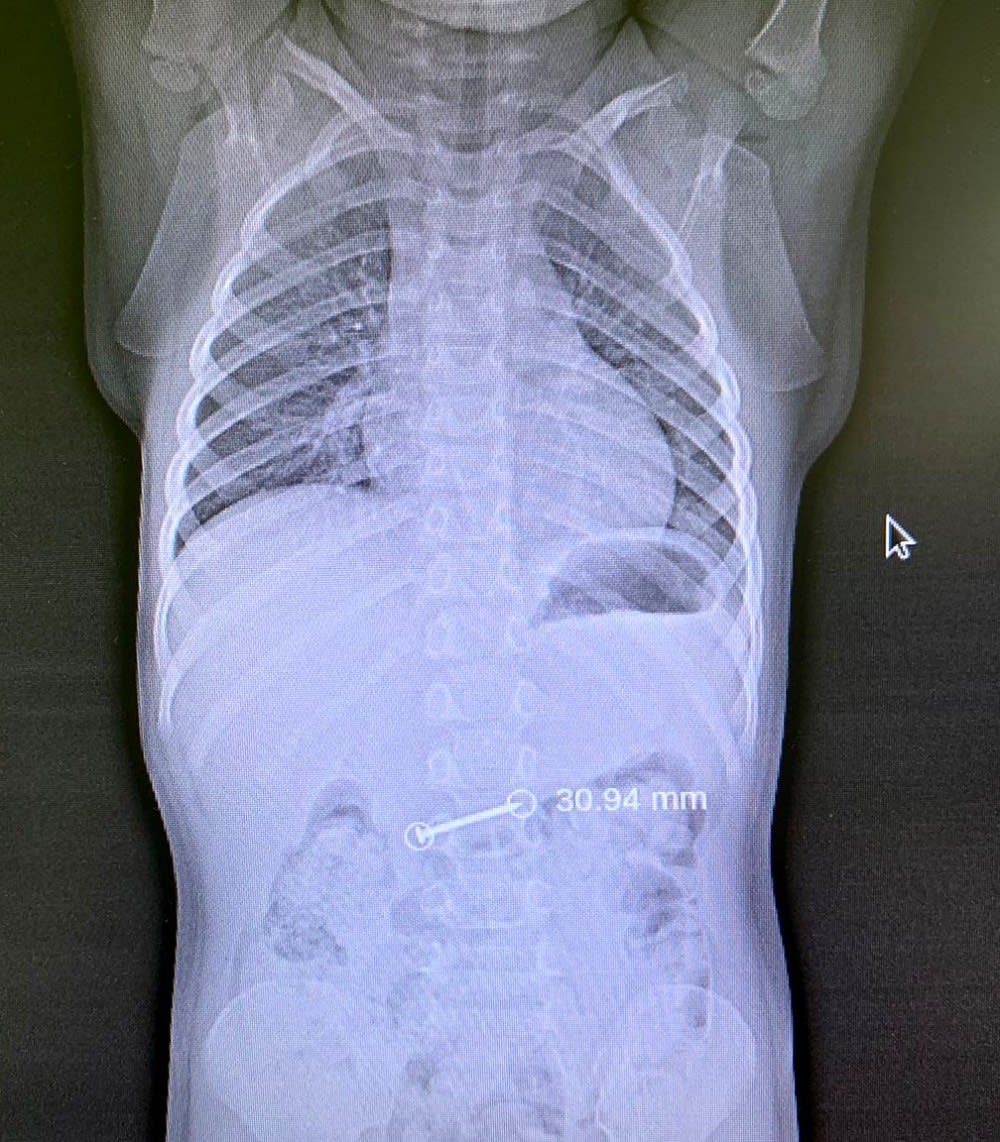

Накануне в больницу родители привезли 8-летнего пациента. Рентген показал наличие инородного предмета в пищеводе, ребенка экстренно направили в отделение эндоскопии. Под наркозом врачи извлекли строительный крючок, затем ребенка передали под наблюдение в отделение хирургии.

В воскресенье врачи отделения эндоскопии буквально догоняли «ускользающий» гвоздь. 3-хлетняя девочка держала его во рту и случайно проглотила. На снимке инородное тело визуализировалось еще в желудке, однако во время проведения эзофагогастродуоденоскопии под наркозом там его уже не оказалось.